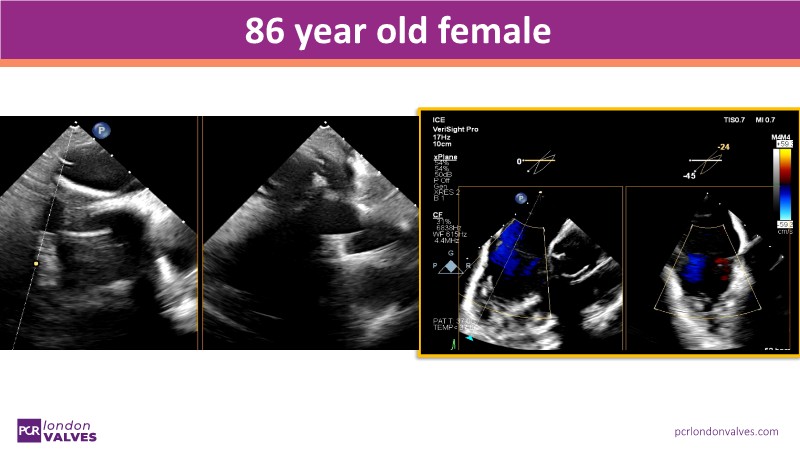

This PCR London Valves 2025 session explores how 3D TEE, 3D intracardiac echocardiography (ICE), and DeviceGuide technology sharpen procedural accuracy, strengthen operator confidence, and streamline decision-making in real time.

The session also includes detailed case analyses—such as Mitral TEER and LAA closure—and dual perspectives from both proceduralists and imagers.